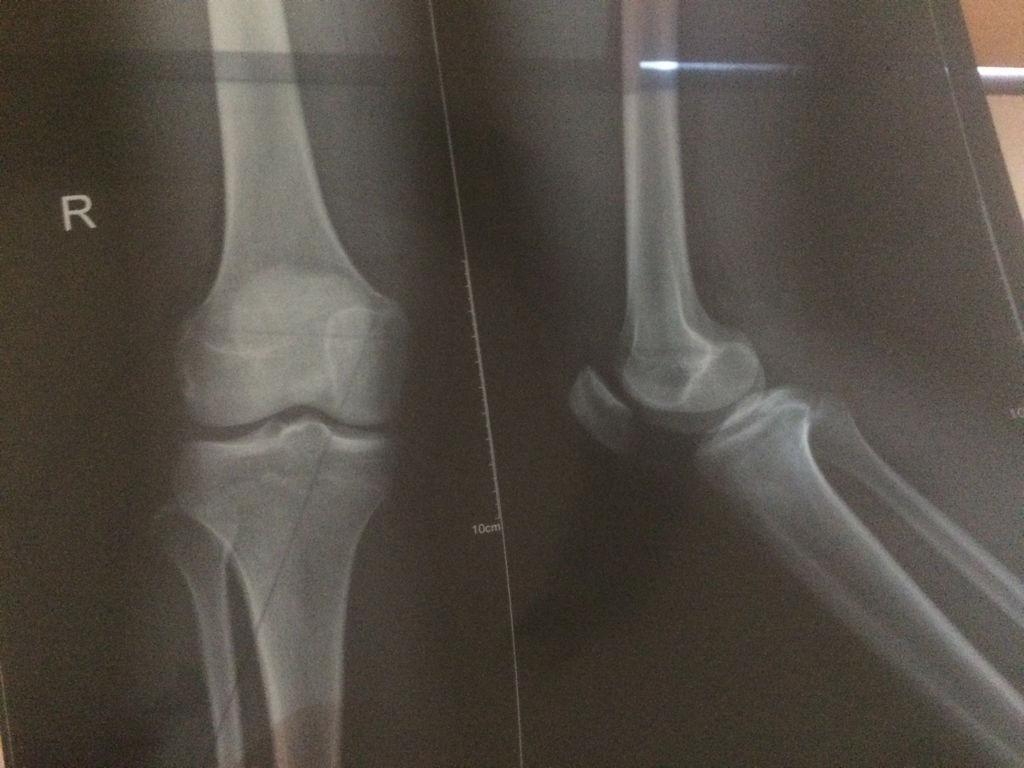

3、 骨密度检查

还有部分家长特别喜欢带孩子去做骨密度检查,想通过这种方法来看看孩子能长得多高,亦或者是想看看孩子有有没有缺钙的症状。

实际上,北京大学人民医院骨科医生吴珺表示:正常孩子一般都不用做骨密度检查,除非孩子有反复骨折或是骨头出现畸变的情况,那么这时需要进行骨密度检查。

而且,目前国际上对儿童骨密度的标准值并没有给出明确规定,各个医院的检测方式也不同,因此检测出的结果也会有所不同。

如果家长们是想知道孩子还能不能再长高,那么应该去做骨垢线检查,而不是骨密度检查。至于是否有缺钙与否,家长们平时可以适当给孩子补充钙元素,等到孩子进入快速发育期时,则再多补充一些。